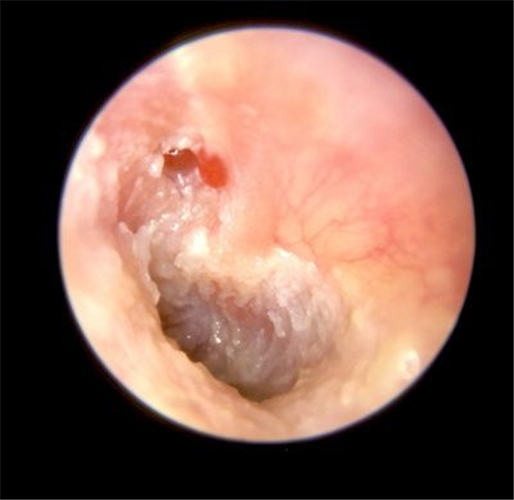

炎症導致鼓膜穿孔

炎症導致的鼓膜穿孔